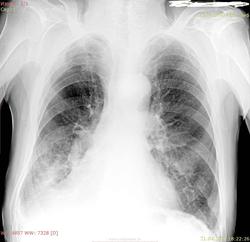

Пациент 1930 г.р., одышка в течение длит времени. Ателектаз н\доли пр легкого? И гидроторакс справа вроде тоже есть.

Гиповентиляция в средней доле справа. Гидроторакса не вижу.

Простите, а почему средней - по боковому главная междолевая щель смещена книзу и кзади?

Жидкости не вижу.Ателектаз,образование нижней доли справа.

Ателектаз скорее. А почему доли? А не м.б. долей, сегментов долей? Иногда м.б. и среднего и частично нижнего и верхнего! Т.е. центральный правого и точка. Но и пневмонию не искл.!

Ателектаз нижней доли

Для легочного сердца контур сердца слева даже немного расширен. Увеличенный правый желудочек иммитирует смещение средостения вправо. Почти уверен, что справа - жидкость. Наверное и отеки на ногах есть.

Мне кажется это все же жидкость по междолевым и в плевральной, форма только причудливая. Ребро не могу понять свежее или нет, архив не открывается. А если ателектаз, почему тогда  по прямой междолевка не подтянута книзу? Кстати, подчеркнута.

Пневмосклерозище, давнишний правосторонний плеврит.